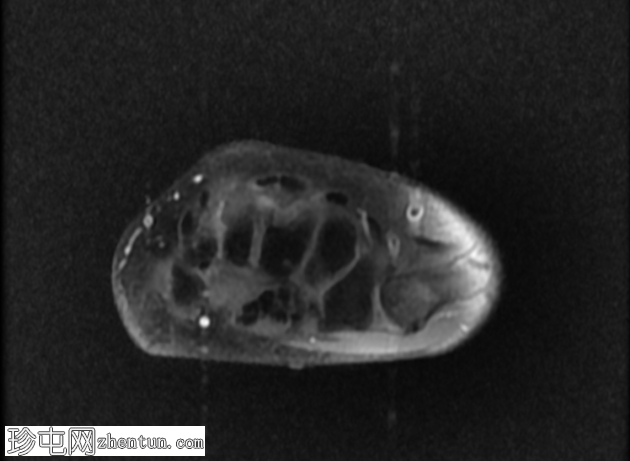

轴向

STIR

无名指和中指明显增大。患者掌骨和指骨骨质增生肥大,并伴有周围皮下脂肪过度增生。

支配患指的正中神经掌侧支纤维脂肪瘤性错构瘤。它们在矢状面序列上呈现意大利面条状,在轴位图像上呈现绳索状。